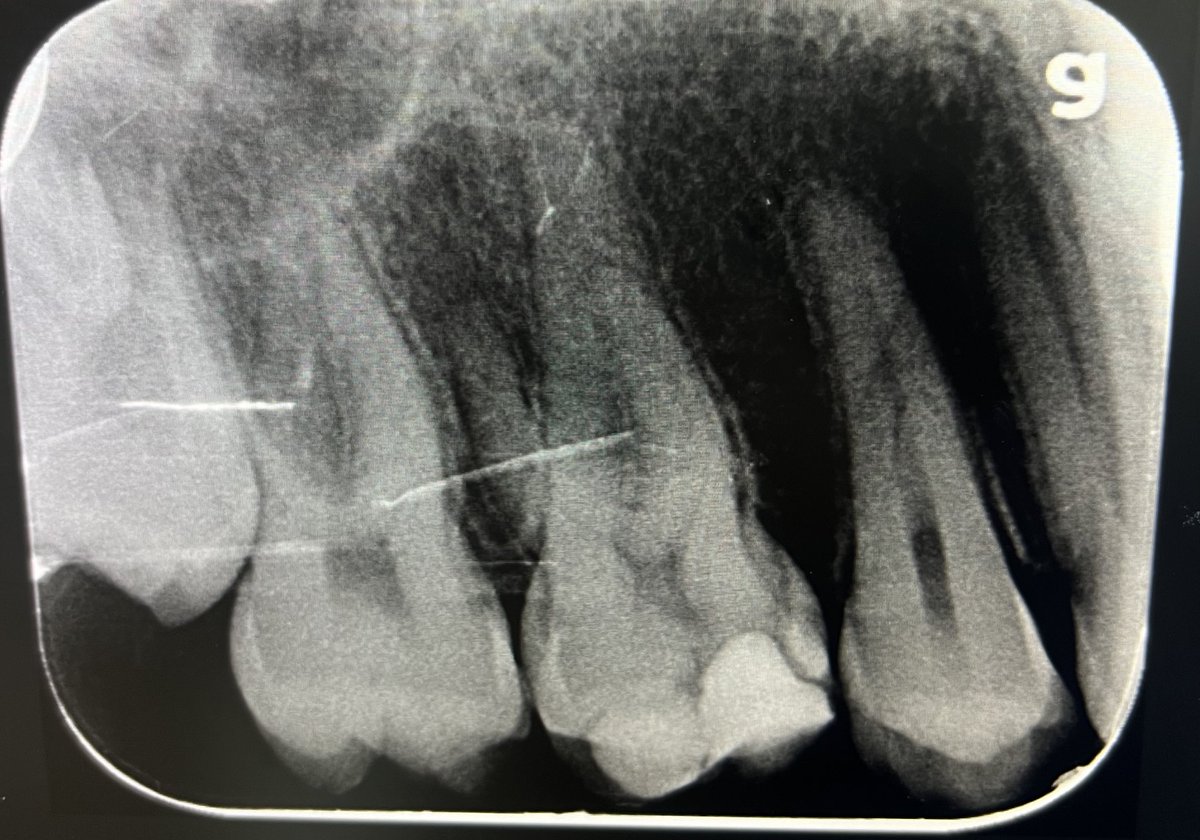

حالة جميلة لصباح اليوم 🙏🏻

Root Canal Treatment #34

Dx:SIP+SAP

Gingival overgrowth and deep caries in the distal wall, Rebuild the distal wall to achieve optimum isolation ✨

Next Step: Crown